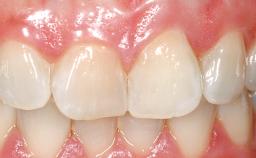

Late Flapless Placement of an Implant in a Maxillary Left Central Incisor Site

Prosthesis Type FDP

Soft Tissue Contour and Volume Slightly compromised